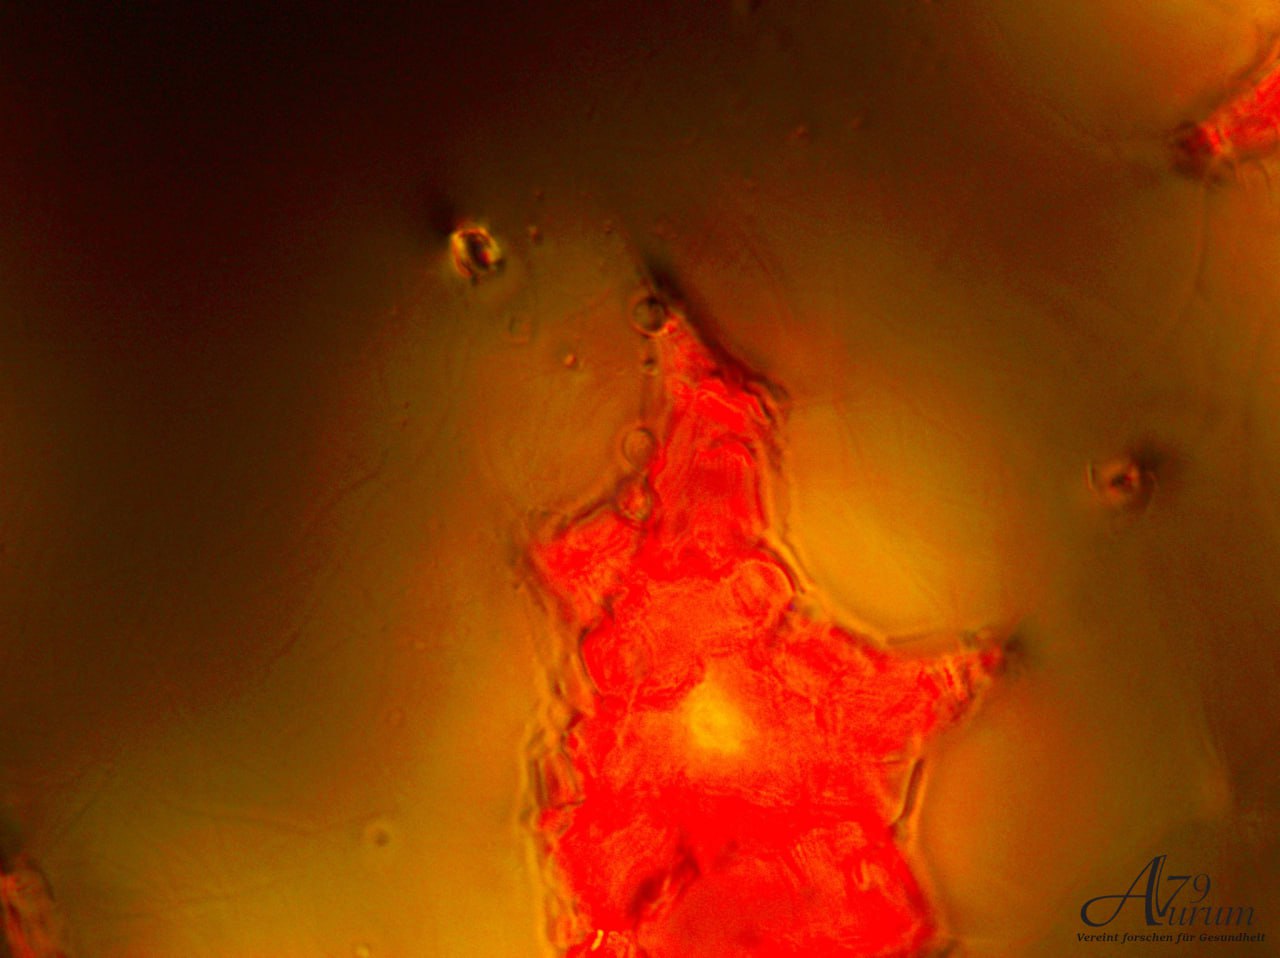

Vitalblutanalyse 1. Tag

Zeigt zahlreiche kreisförmige Strukturen (Erythrozyten) mit variierender Intensität. Einige Zellen scheinen aggregiert, andere einzeln verteilt. Weitfeld-Okulare mit 10-facher Vergrößerung & 40x Objektiv